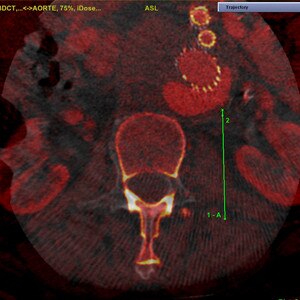

INTERVENTIONS AU NIVEAU DU RACHIS

Guider